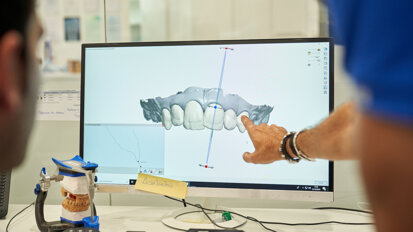

Wokół leczenia implantoprotetycznego krąży bardzo wiele mitów. Najczęstsze skojarzenie to sztuczna szczęka seniora trzymana w szklance obok łóżka. Noszenie ruchomych uzupełnień protetycznych nie jest jedynym rozwiązaniem w odbudowie brakujących zębów. Współczesne zabiegi implantologiczno-protetyczne pozwalają znacząco poprawić jakość życia pacjenta. Umożliwiają zmianę lub poprawę wyglądu zębów szybko, bezboleśnie i z wykorzystaniem nowoczesnych oraz przystępnych cenowo rozwiązań przy użyciu lekkich i estetycznych materiałów uzupełniających.

„Do specjalisty protetyka warto zgłosić się nie tylko w przypadku pojedynczych lub większych braków zębowych, ale również wtedy, gdy dojdzie już do całkowitego bezzębia. Porada lekarska wskazana jest również dla osób, które doświadczyły urazów mechanicznych, mają znaczące i długoletnie problemy związane z chorobą próchnicową lub patologicznie startymi zębami, wynikające zarówno z nieleczonych wad zgryzowych, jak i zaburzeń w układzie stomatognatycznym. W ramach działań protetycznych możemy również przeprowadzić zabiegi estetyczne takie jak korekta kształtu, koloru czy wysokości uzębienia” – zaznacza Marta Markunina.

„Pierwszy krok w leczeniu to przede wszystkich kompleksowa diagnoza, która pozwala określić potrzeby i dobrać metody działania indywidualnie z uwzględnieniem stanu zdrowia, możliwości finansowych i oczekiwań estetycznych pacjenta. Niestety, wiele osób nie dociera na badanie z powodu głęboko zakorzenionych w świadomości mitów związanych z usługami implantoprotetycznymi” – mówi dr n. med. Marta Markunina.